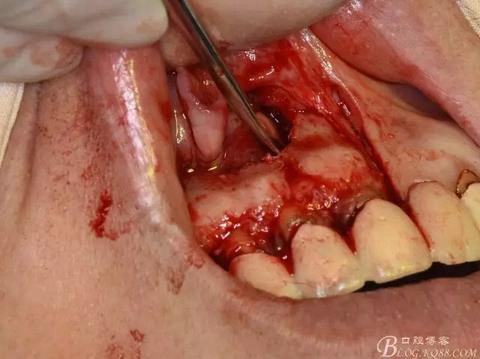

圖7. 分別在13的遠中和11的近中做垂直切口加齦溝內(nèi)水平切口,形成梯形瓣

圖8.翻開梯形瓣